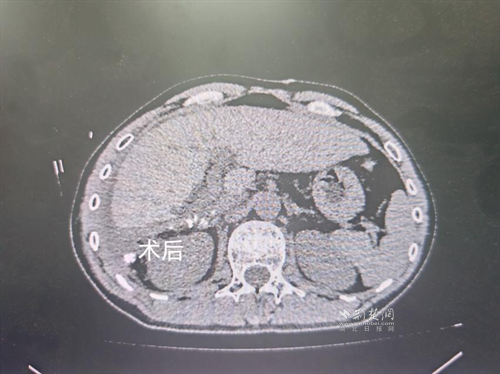

经过肝胆外科牵头组织的多学科MDT会诊,团队确认其适合接受当前国际先进的钇90树脂微球选择性内放射治疗。治疗仅一个月后,患者病灶即从10cm缩小至6cm;术后六个月复查显示,病灶体积进一步缩小近40%,影像学检查提示完全缓解,临床分期成功转化,达到手术切除标准。